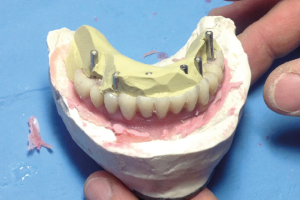

Il tecnico Elia Amicuzi ha realizzato la protesi presso lo studio per ridurre i tempi e permettere la prova in bocca della protesi prima di finalizzarla. Gli analoghi-moncone sono stati avvitati ai transfer e gli insiemi analoghi-transfer sono stati riposizionati nell’impronta (Figg. 33, 34).

Per una maggiore veridicità il tecnico ha applicato della gengiva finta e realizzato il modello master (Figg. 35, 36) per la messa in articolatore (Fig. 37).

Ha fissato le cappette in titanio sopra gli analoghi-moncone e le ha tagliate in altezza (Figg. 38, 39).

Per rendere la protesi più rigida durante la prova ha realizzato un rinforzo in resina prima di eseguire la disposizione dei denti con la cera (Figg. 40-43).